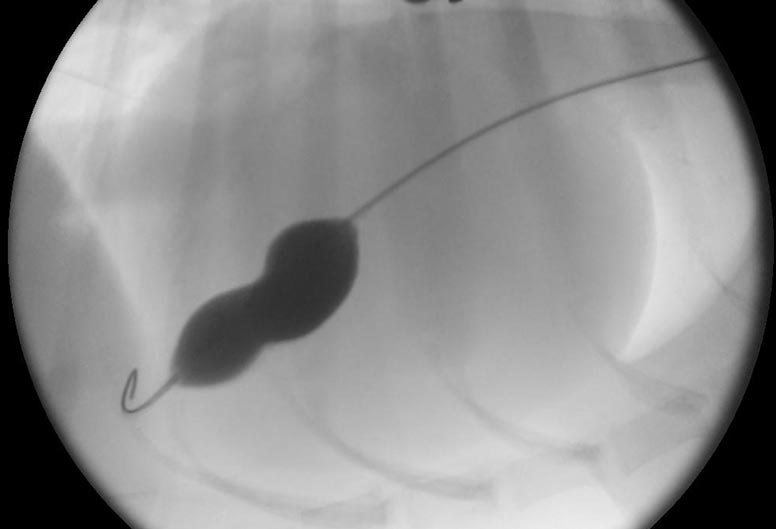

Tobi, who treated Leo, said; “Although this disease cannot be cured, a procedure called Balloon Valvuloplasty can be performed to alleviate symptoms. Balloon valvuloplasty involves placing a balloon across the narrowed valve, which is then inflated to stretch the valve open. This is a “keyhole” procedure, performed via a tiny puncture in the Jugular vein.”

Tricuspid stenosis is rare, whereas narrowing of the pulmonic valve (Pulmonic Stenosis) is much more common. Balloon valvuloplasty for pulmonic stenosis a routine procedure for specialist veterinary cardiologists, whereas balloon dilation of the tricuspid valve is uncommonly performed. The tricuspid valve requires very careful handling and a lot of interventional experience as ‘overdilation’ can result in a very leaky valve, potentially making the condition worse rather than better.’